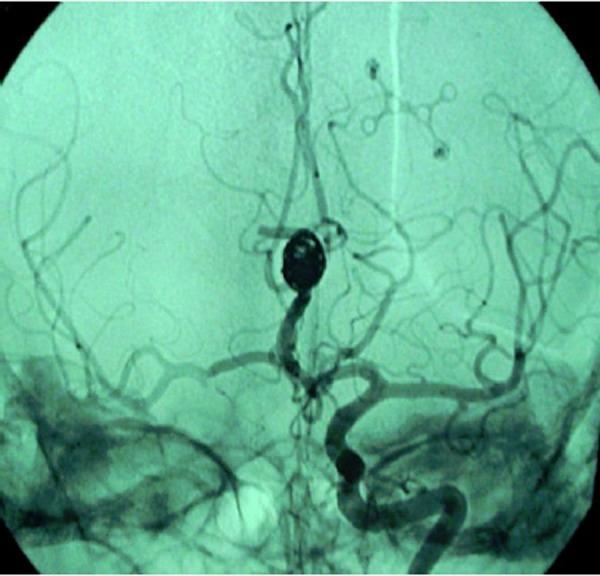

Pregnancy is a recognized risk factor for aneurysmal subarachnoid hemorrhage (SAH). Headache is very frequent in normal pregnancy and it is a common sign shared between several intracranial diseases. We present a case series of 10 women in the third trimester of pregnancy admitted to our intensive care unit (ICU) with neurological signs and symptoms. 4 of these patients were diagnosed with SAH. Data in this study suggest that a timely diagnosis and an appropriate treatment is crucial for mother and baby.

妊娠是动脉瘤性蛛网膜下腔出血(SAH)的一个公认危险因素。头痛在正常妊娠中非常常见,并且是几种颅内疾病共有的常见症状。我们报告了一组病例,10名妊娠晚期妇女因神经体征和症状入住我们的重症监护病房(ICU)。其中4名患者被诊断为SAH。本研究中的数据表明,及时诊断和适当治疗对母婴至关重要。